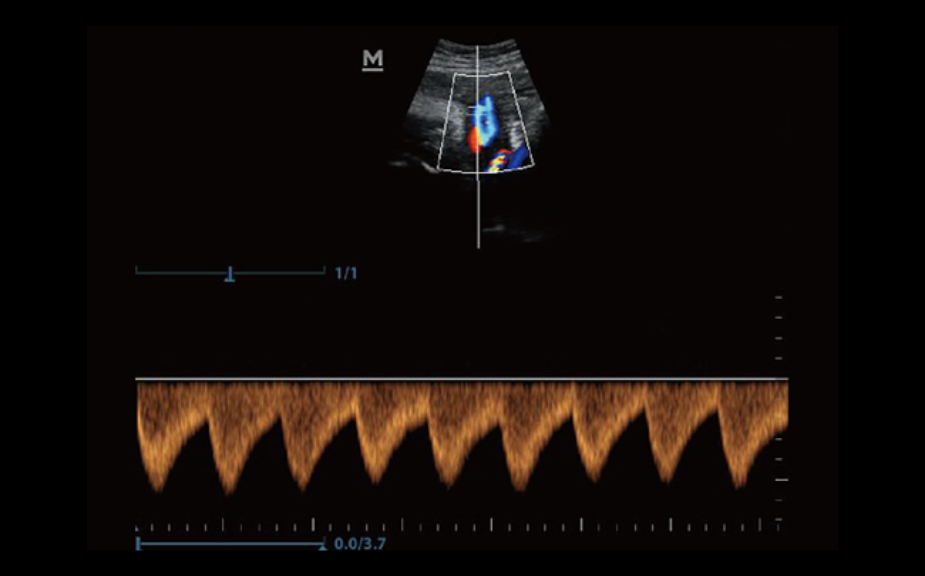

3B/4B G?r├╝nt├╝leme

G?r├╝nt├╝n├╝n her y?nden h?zl? ve kolay bir ?ekilde izlenebilmesini sa?layan 3B/4B ?evirme ve E?itleme ?zelli?i ile